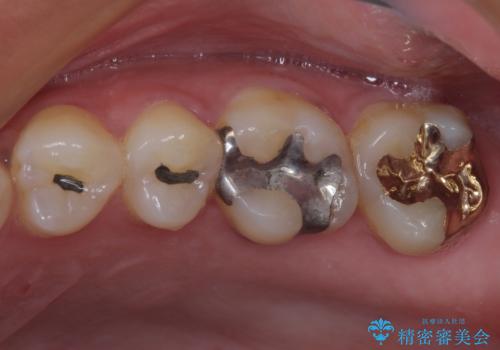

高さの足りない奥の銀歯をセラミッククラウンに

- 奥歯の銀座を白くしたいとのことで来院された患者様です。

右下の奥歯は、土台の高さが足りずセラミッククラウンを装着することが困難であったため、歯冠長延長術と歯肉弁根尖側移動術を行い、十分な土台の高さと角化歯肉幅を獲得することとしました。

また、必要に応じて、根管治療を行うこととしました。

右下の手術は、術後の痛みが非常に強いものとお伝えしてはいたものの、予想以上に痛かったようでご迷惑おかけしてしまいました。

治療終了時に、治療前との比較写真をご覧いただいたところ、土台の高さが十分に増したことに驚かれ、その結果として銀歯がなくなったことで審美面が改善されたことに大変満足していただけました。